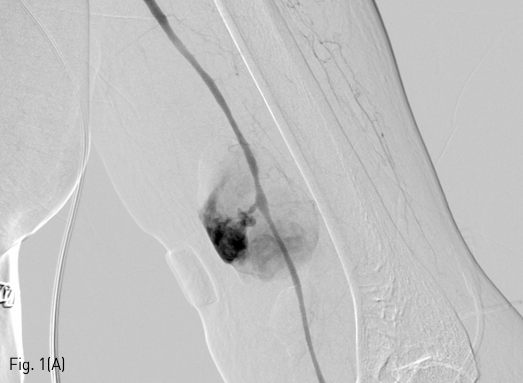

왼쪽 위팔동맥에 혈종 혹은 가성동맥류의 가능성을 염두에 두고 혈관조영술을 시행하기로 하였다. 오른쪽 총대퇴동맥에 7Fr sheath를 삽입한 후, 5F Head Hunter catheter를 이용하여 왼쪽 쇄골하동맥까지 접근한 후, 왼쪽 위팔동맥의 혈관조영술 영상을 얻었다 (Fig. 1A). 천자 부위에서 약 2mm 크기의 목을 갖고 있는 약 60mm x 35mm 크기의 가성동맥류가 관찰되었다. 이를 치료하기 위해 해당 부위를 완전히 덮을 수 있는 스텐트-그라프트를 설치하기로 하였다. 근위부 위팔동맥의 직경은 약 3.5mm였지만, 저혈량 상태가 개선되고 생체징후가 안정화되면 동맥 직경이 커질 것을 감안하여 6mm 스텐트-그라프트를 설치하기로 하였다. 260cm 길이의 stiff guidewire (Glidewire, Terumo, Tokyo, Japan)를 사용하여 6mm-5.5cm Viabahn 스텐트-크라프트 (W. L. Gore & Associates, Flagstaff, Arizona, USA)를 가성동맥류의 목 부위를 충분히 덮도록 설치하였다 (Fib. 1B). 혈관조영술 영상에서 소량의 내강유출이 관찰되어 (Fig. 1C), 5mm Mustang 풍선 카테터 (Boston Scientific, Natick, Massachusetts, USA)을 이용하여 스텐트-그라프트의 근위부와 원위부에 대해 혈관성형술을 시행하였다. 다시 촬영한 혈관 조영술 영상에서 내강유출은 소실되었다.

Fig 1C

(C) Post-procedure angiogram shows a small endoleak (arrow) to the pseudoaneurysm. 5-mm balloon angioplasty was performed (not shown).